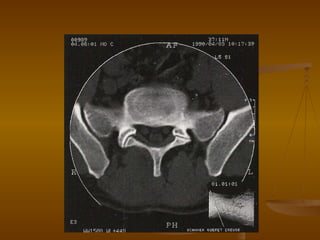

Микционное исследование уретры Исследование с мочеиспусканием после внутривенного введения контрастного препарата или катетеризации мочевого пузыря 3 D  реконструкция Мультипланарная  реконструкция Виртуальная  цистоуретроскопия Мочевой  пузырь Уретра

Микционное исследование уретрыИсследование с мочеиспусканием после внутривенного введения контрастного препарата или катетеризации мочевого пузыря 3 D реконструкция Мультипланарная реконструкция Виртуальная цистоуретроскопия Мочевой пузырь Уретра